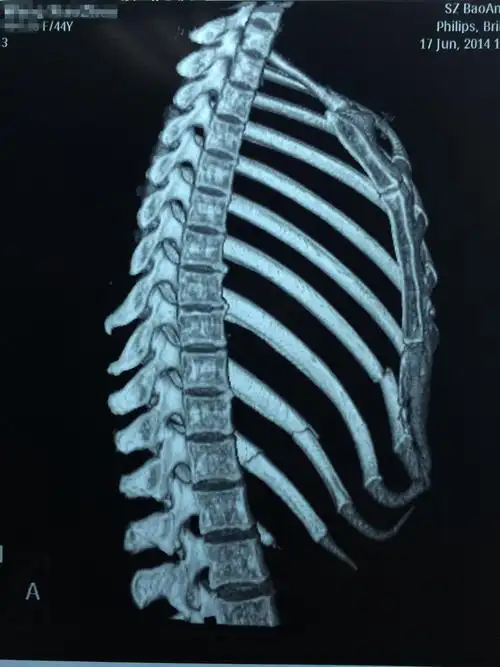

问:肋骨骨折断端重叠(详见ct报告单,图片)